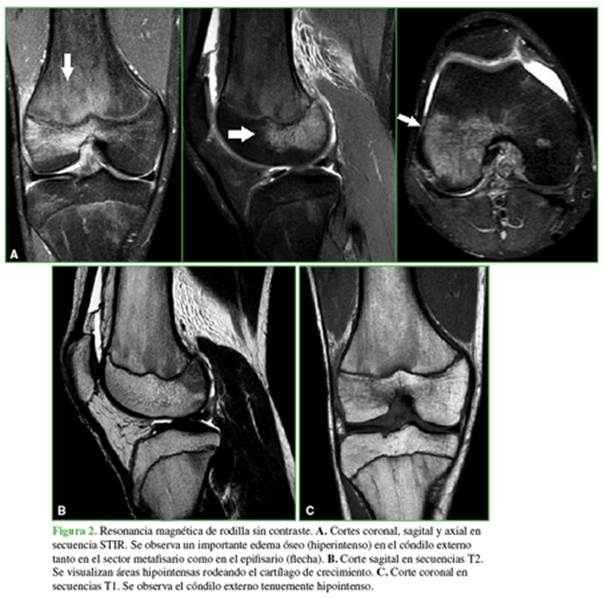

En las radiografías, no se identifican lesiones aparentes (Figura 1). En la resonancia magnética, se puede observar un importante edema en el cóndilo femoral externo, con compromiso de los sectores metafisario y epifisario, sin lesión del cartílago de crecimiento, visible preferentemente en las secuencias sensibles a los líquidos y con supresión grasa (STIR) (Figura 2A).

Se puede observar una baja señal en las secuencias T2 y una señal intermedia en las secuencias T1 (Figura 2B y C).